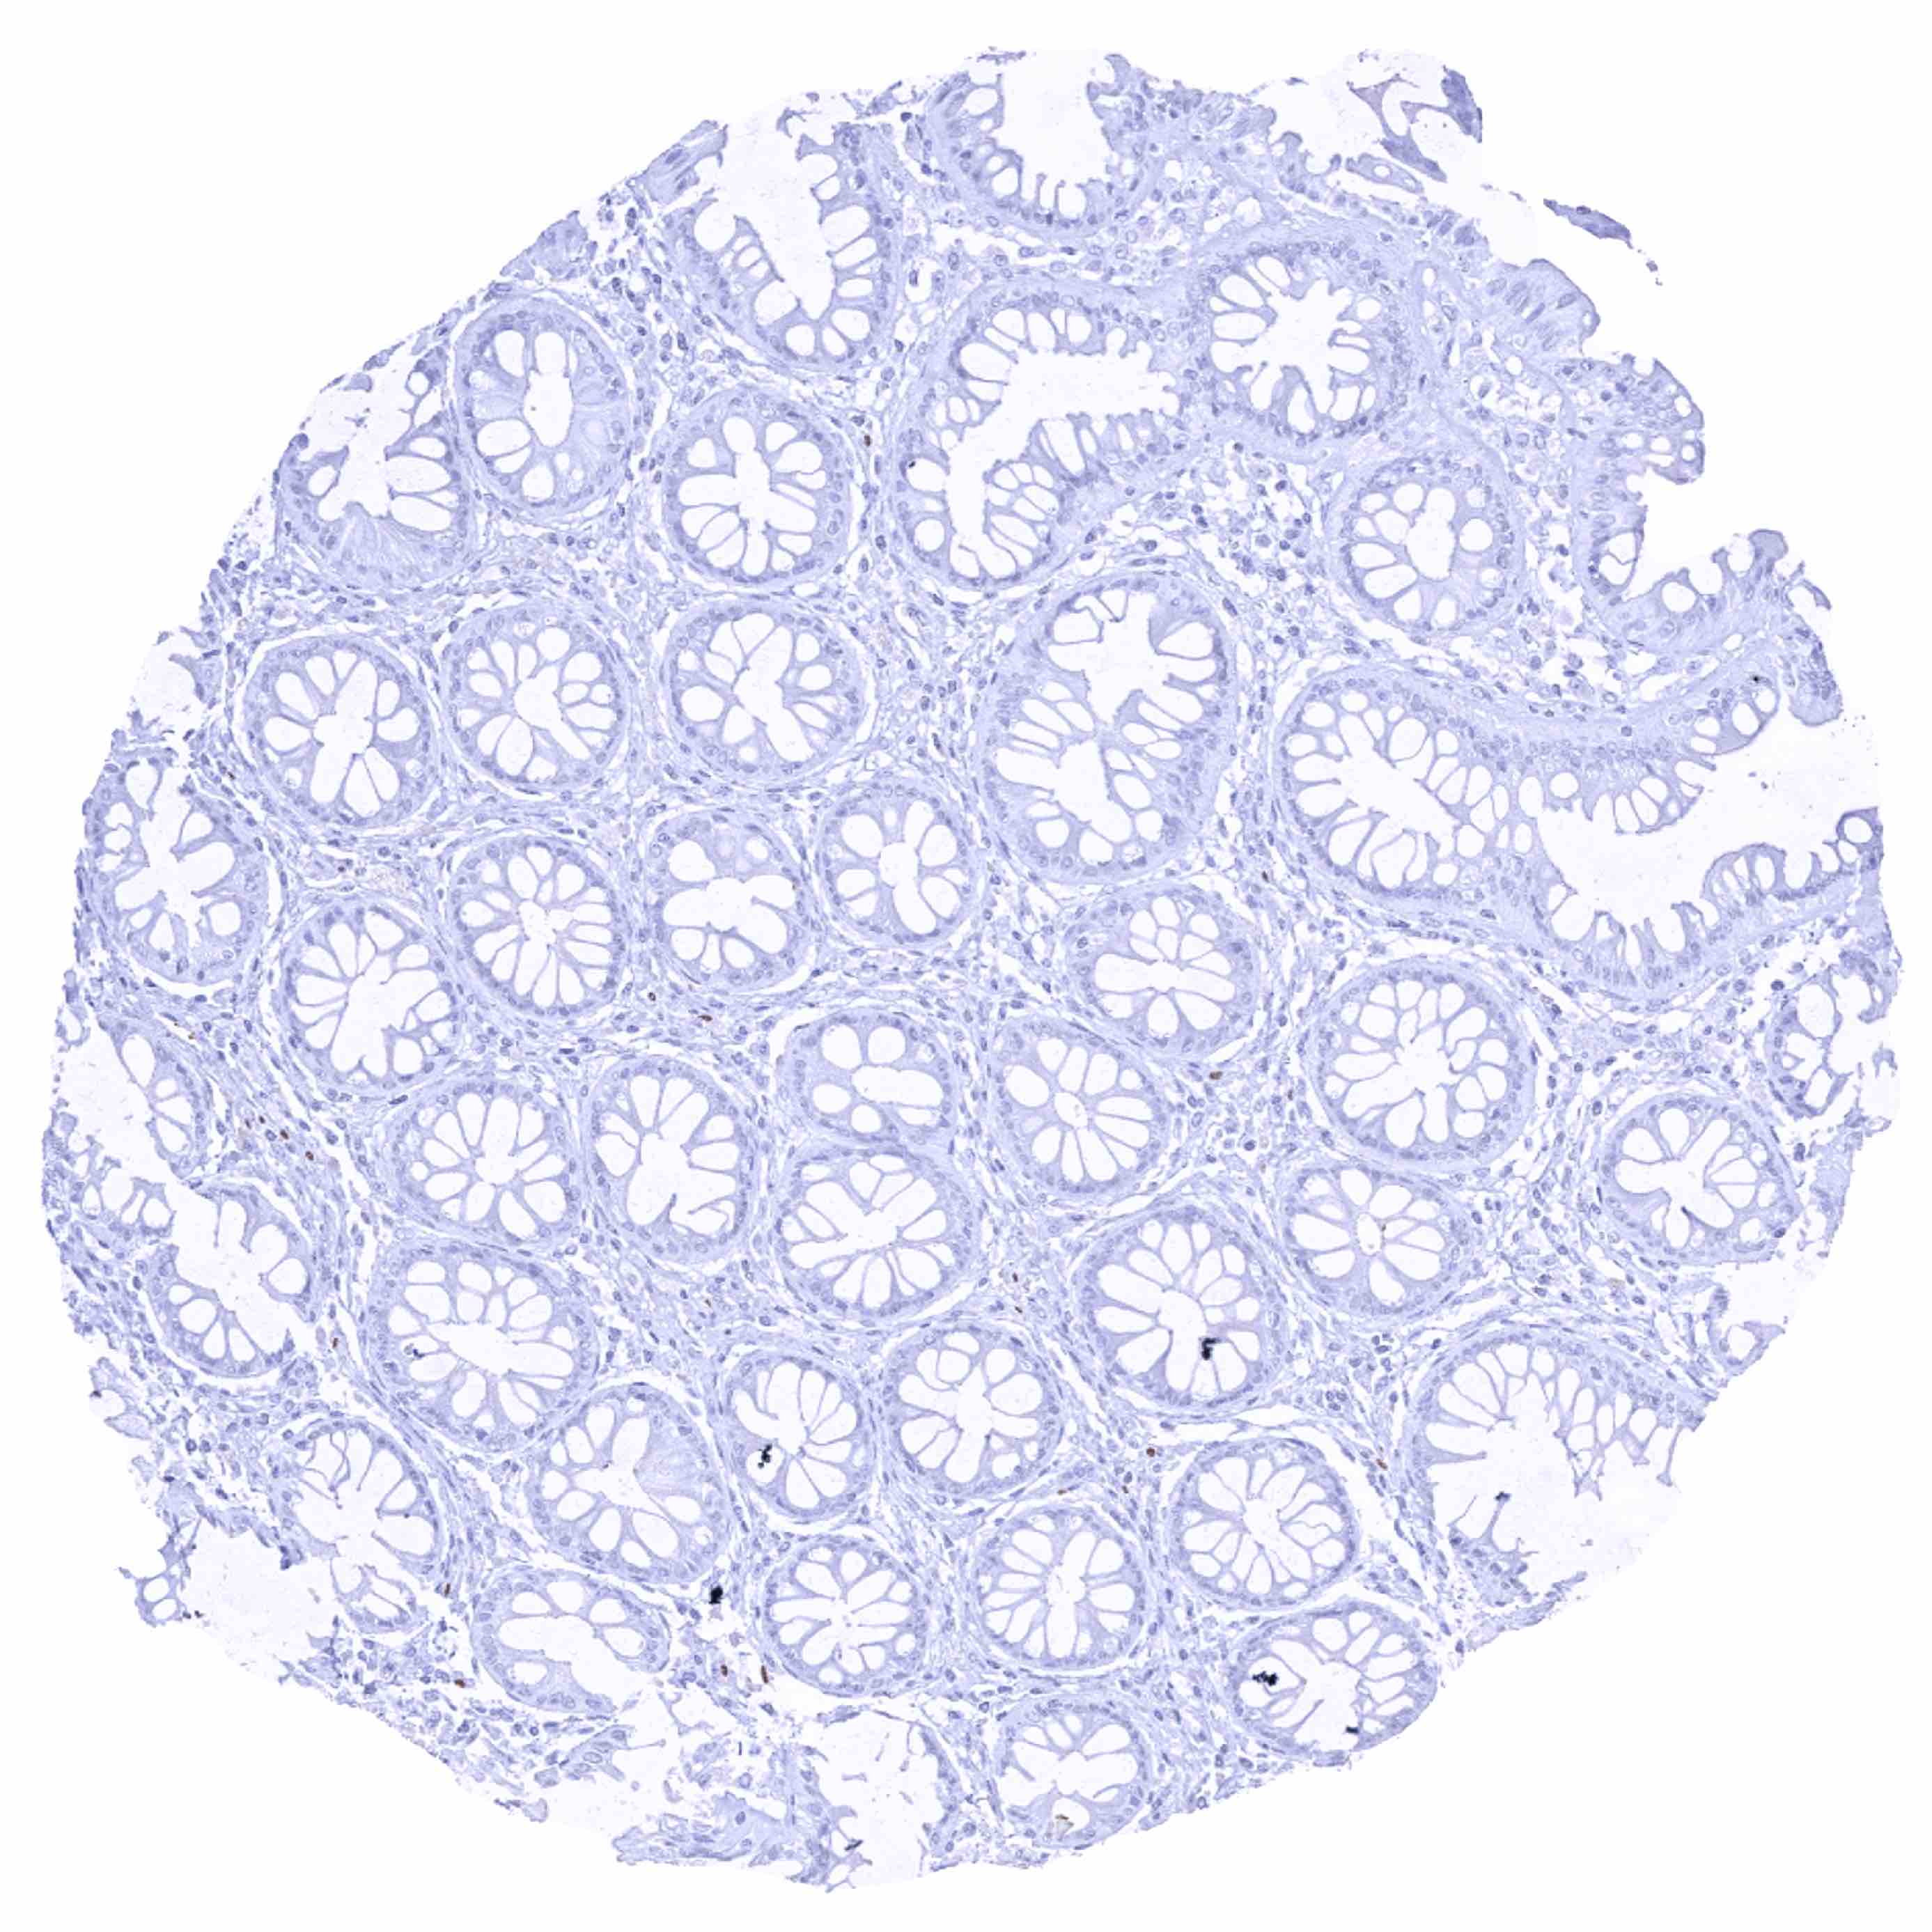

Colon descendens, mucosa

Colon descendens, muscular wall – Strong SOX2 positivity of a large fraction of intramural ganglion cells as well as of few spindle shaped (neural_) cells in the muscular wall